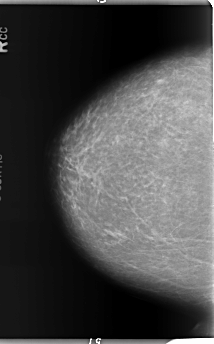

B_3368_1.RIGHT_CC

RIGHT_CC LINES 5848 PIXELS_PER_LINE 3624 BITS_PER_PIXEL 12 RESOLUTION 50 NON_OVERLAY

LESION_TYPE MASS SHAPE LOBULATED MARGINS CIRCUMSCRIBED

ASSESSMENT 3

SUBTLETY 4

PATHOLOGY BENIGN